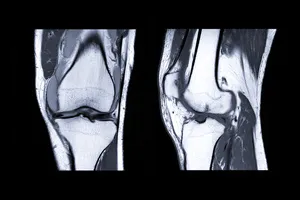

- 심각한 연골 손상

- 관절염 말기